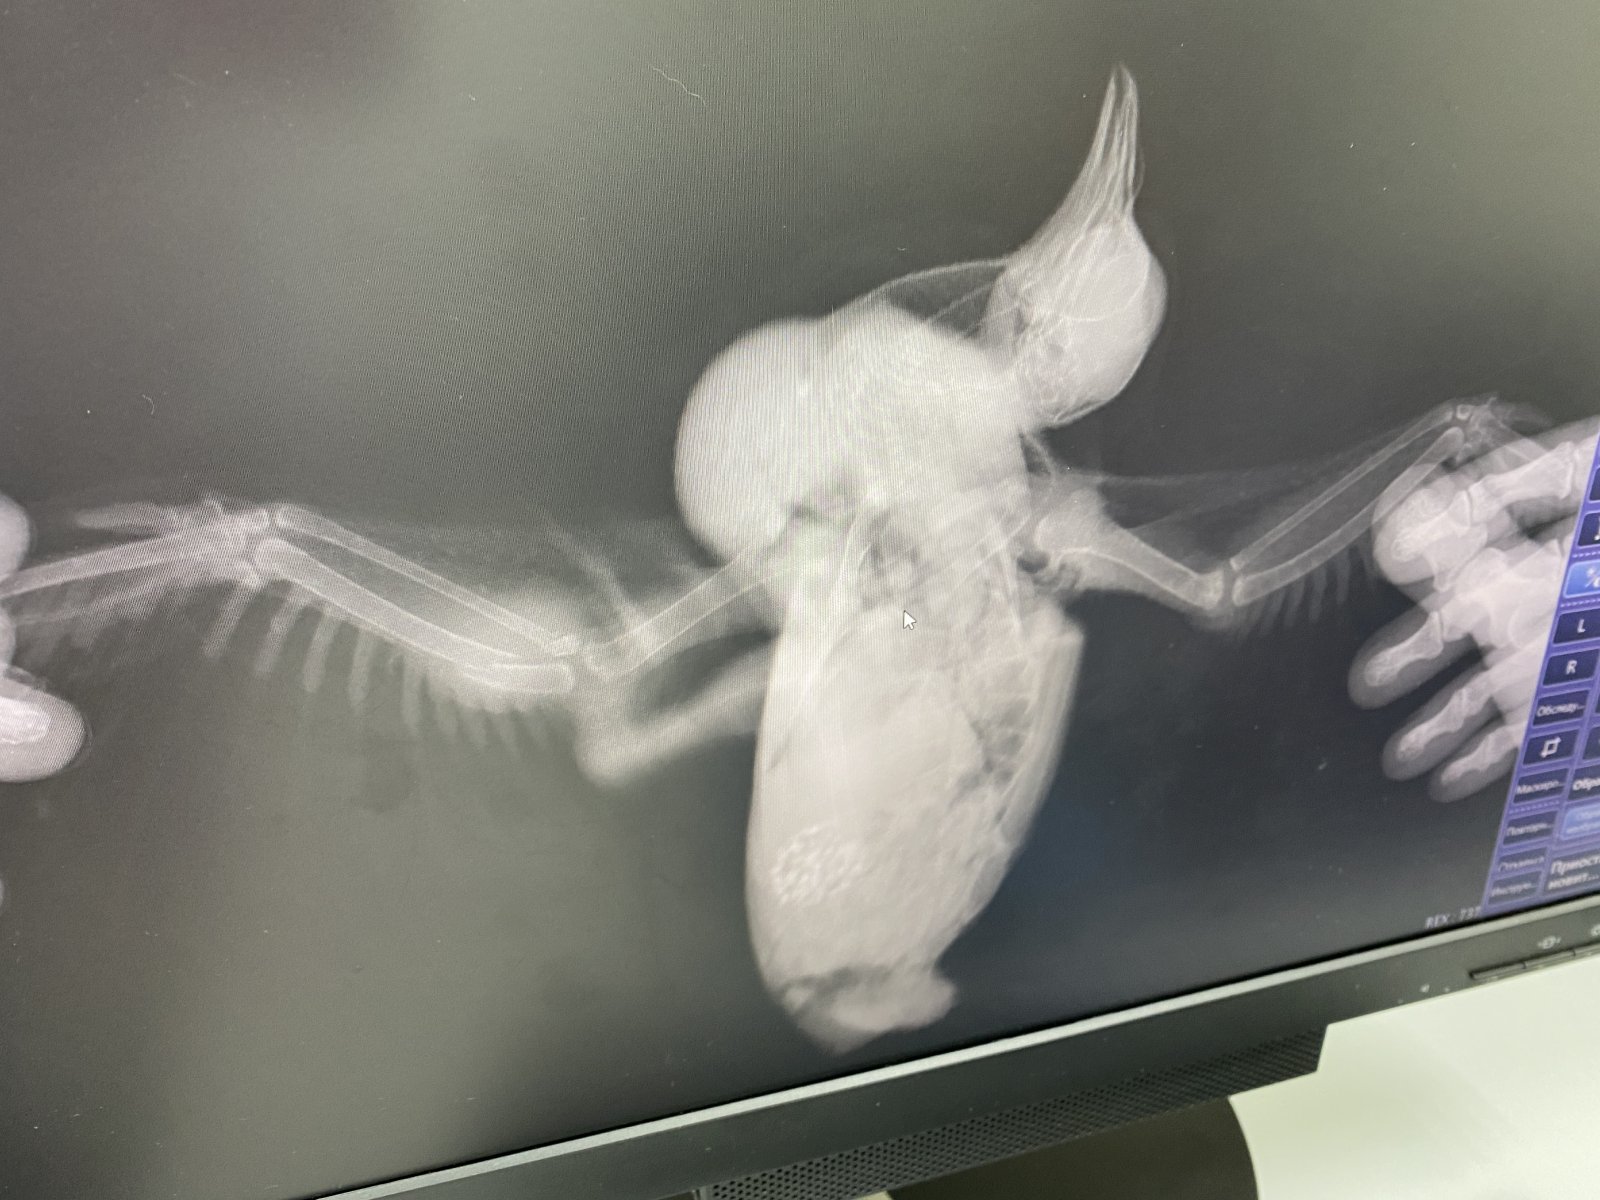

spring__rain@mail.ru Опубликовано 15 июня, 2022 Автор #8 Опубликовано 15 июня, 2022 10 часов назад, Шер Ами сказал: Вроде кости незадеты, значит цефтриаксон ненужен. Запох есть неприятный от раны? При открытой ране, если это мягкие ткани, то энрофлоксацин /ветеринарный/ вполне подойдёт. параллельно антибиотику Флуконазол /50 мг./ упаковку купить. @spring__rain@mail.ru кости задеты? Или это рана на мышцах? вроде нет запаха, но у меня с обонянием проблемы, я могу и не почувствовать. Но вроде гнилью не воняет или чем-то резким. Раны Мелкие , точечные, кости визуально не задеты, крыльями машет активно , но одно приспущенно связки и ткани записан на рентген, через 8 часов уже буду знать результат отпишусь. про лекарства промываю смесью демиксида, новокаина и демоксидина, сейчас примочку из него сделала. (нашла тут на сайте описание как делать смесь эту) учу клевать, частично получается , докармливаю пока просит пьет в конце стал чистить пёрышки Вымыла его всего , лапы чистые фекалии потом сфотографирую, он разный Иногжа с пеной(может есть гельминты, визуально невидноС но пена вчера была сейчас сформированный кал Внутрь даю офлосан 0,3 мл два раза в день (утро раннее и поздний вечер ) днем и в вечером даю нурофен детский + пробиотик и гамматоник в пищу. иногда присыпаю ранки банеоцином тонко 5 часов назад, маленький принц сказал: чем кормить и что НЕЛЬЗЯ https://www.mybirds.ru/forums/topic/111964-sizarikinarodru/ как кормить если не ест сам https://www.mybirds.ru/forums/topic/34206-prinuditelnoe-kormlenie/ про голубят http://www.mybirds.ru/forums/index.php?showtopic=33566 как держать дома https://www.mybirds.ru/forums/topic/122247-golubi-tozhe-domashnie-pitomtsy/ когда начнёт летать чтобы не бился об стёкла познакомьте со окнами и зеркалами: поднесите к стеклу так чтобы коснулся грудью и клювом а затем дайте потрогать самому ВНИМАНИЕ при любых манипуляциях с птицей голову держать ВЫШЕ зоба чтобы случайно не захлебнулся содержимым (если же нужно например для рентгена уложить птицу на спину то зоб должен быть пуст для этого за три часа до переворачивания на спину НЕ кормить и НЕ поить) накормив через три часа ощупайте зоб как найти зоб: ведите вдоль кости киля пальцем вперёд спереди между килем и шеей будет ямка а в ней мешочек = зоб если зоб опустел то накормите ещё если не опустел то напишите на форум сколько ещё осталось еды в зобу до полного освобождения зоба НЕ кормить кормить только при ПУСТОМ зобе (если накормить при не пустом зобе то есть риск что зоб остановится и птица захлебнётся рвотой) так же через три часа после кормёжки сделайте фото помёта на белой бумаге при хорошем освещении для ориентировки взрослому в день нужно полторы-две столовые ложки сухого зерна с горкой (почтовому голубю который много летает в день нужно три столовые ложки с горкой) и это количество нужно считать до варки каши так как при варке зерно набухает и впитывает воду малышам нужно давать пробиотик (с водой через шприц без иглы или вместе с кашкой) лучше всего бифудумбактерин БЕЗ сахара и БЕЗ глюкозы (на кончике ножа) если такой не найдёте то можно Линекс (содержимое одной капсулы на день) и лучше пробиотик не "форте" а обычный так как в форте бывают не всегда подходящие птицам добавки (например бывает сахар) в какой дозировке даёте? кости целые? Рентген сделают через 8 часов, сфотаю , напишу сюда. Мне не нравится шишка или припухлость на крыле. На фото видно ее, она сине-зеленая

маленький принц Опубликовано 15 июня, 2022 #9 Опубликовано 15 июня, 2022 ВНИМАНИЕ за три часа до рентгена НЕ кормить и НЕ поить чтобы при переворачивании на спину не мог захлебнуться содержимым зоба помимо рентгена крыла сделайте и рентген бедра 1

Шер Ами Опубликовано 15 июня, 2022 #11 Опубликовано 15 июня, 2022 Перелом открытый или закрытый? Рана, кровь есть? неприятный запох есть из раны? Если перелом открытый, то антибиотик тогда. Если перелом закрытый, то антибиотик ненужно. Дозировку на цефтриаксон дам, если что. @spring__rain@mail.ru то чёрное, это что? Кровь запёкшаяся?

spring__rain@mail.ru Опубликовано 15 июня, 2022 Автор #12 Опубликовано 15 июня, 2022 Перелом закрытый . Да. Кровь запекшаяся Запаха нет вроде никакого обычно все пахнет, я давала офлосан это офлоксацин вроде фитохинолы (если не ошибаюсь) как шину накладывать ? Только доктора знают ?